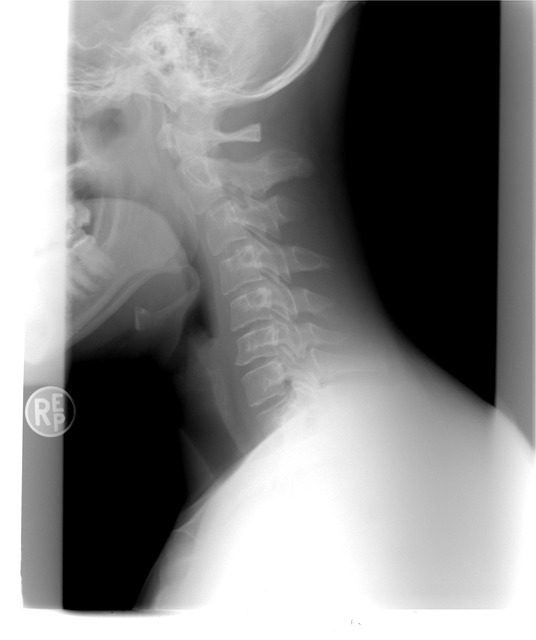

주변을 둘러보면 갑상선에 대한 질병을 흔하게들 많이 들어보셨거나 볼 수 있으실 거예요. 갑상선은 우리 목에 위치해 있는데요. 신진대사에 필요한 갑상선 호르몬을 분비하는 내분비기관을 말합니다.

갑상선 목부음은 갑상선종으로 불리우는데요. 이게 크기가 커지거나 통증이 심해지면 숨을 쉬거나 음식을 삼키는데 불편함이 생겨 일상생활 속에서 많은 불편함을 느낄 수 있다고 해요.